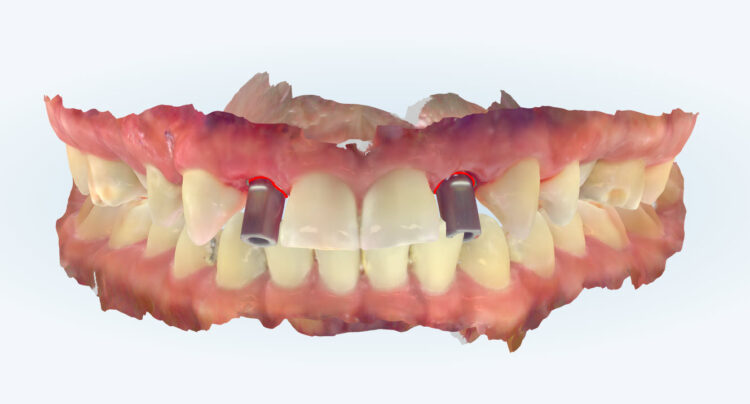

Post-surgical healing and impressions (August 2023)

A week after the surgery, the patient was seen for a healing review, during which X-rays were taken and sutures were removed. After sufficient healing, the patient returned for an impression appointment, where the temporary teeth were removed and scans were taken to fabricate the final crowns.